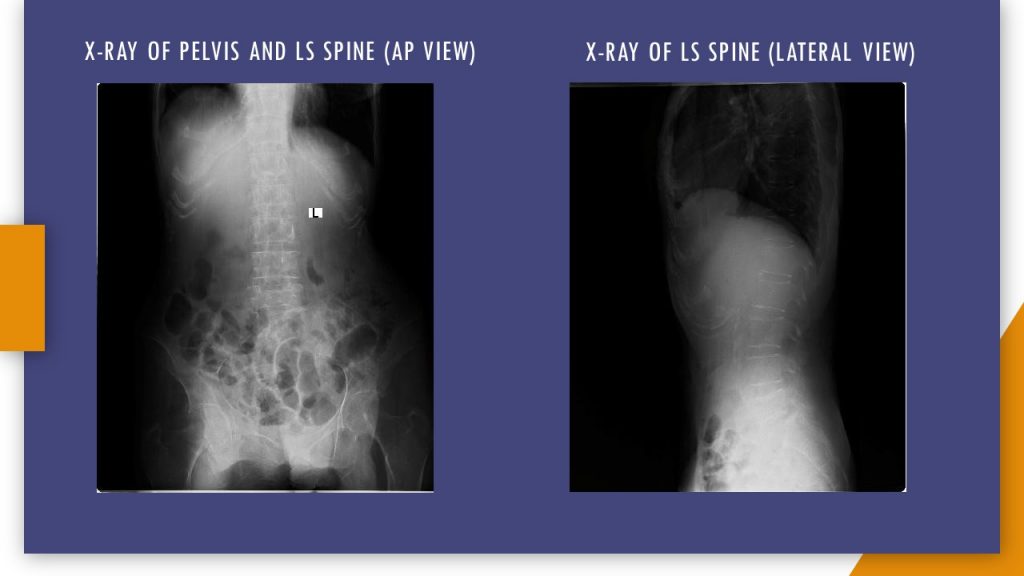

The patient was initially treated for deforming polyarthritis. She was on alternative treatment, but not on any of the DMARDs. Negative ANA, elevated CRP, and deforming arthritis rule out the possibility of SLE. The patient had severe dry mouth, suggestive of Sjogren's syndrome. The patient's RF titres were high and ANA was negative. There were erosions in hand X-ray and clinical features suggestive of RA. These findings indicate the probability of developing Sjogren's syndrome, secondary to RA. The peripheral smear was not suggestive of large granular lymphocyte. In view of these observations, the diagnosis could be concluded as Felty syndrome.